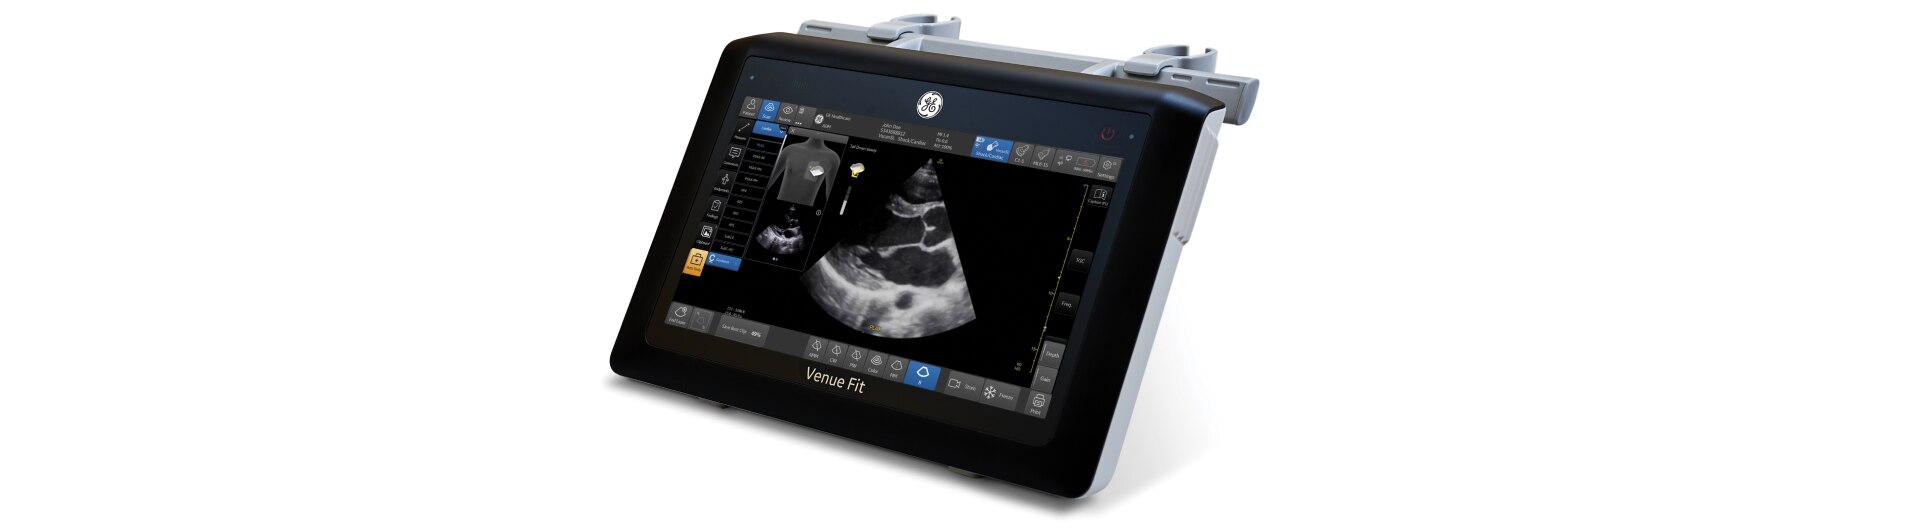

Tanto si busca un modelo adaptable que pueda utilizar en un carro, en la mesa o en la pared, como si prefiere una consola con una pantalla grande, hay un sistema versátil, robusto y sencillo adecuado para su punto de atención al paciente.